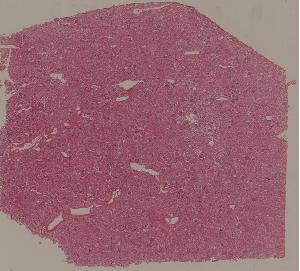

62.急性普通型病毒性肝炎

63.慢性活动性肝炎

64.急性重型病毒性肝炎

65.亚急性重型病毒性肝炎

66.活动性结节性肝硬化

67.非活动性结节性肝硬化

68.胆汁性肝硬化

69.肝细胞性肝癌